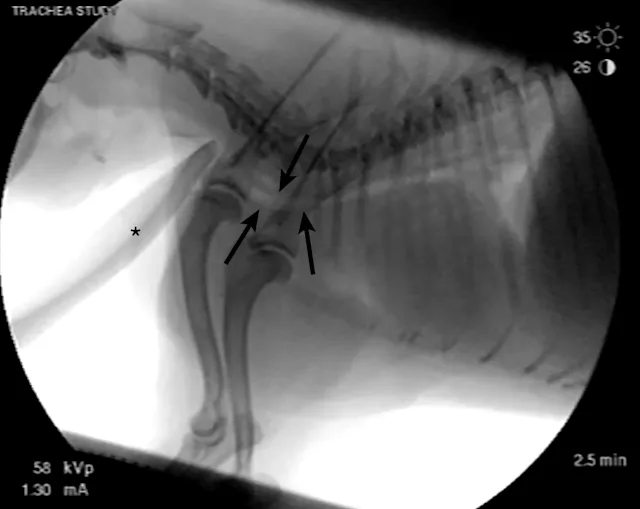

On examination, the dog was panting with expiratory effort and crackles auscultated diffusely. She exhibited an occasional goose-honking cough and retch. Her body temperature was normal. Radiography (Figures 1 and 2), fluoroscopy (Figure 3), and bronchoscopy (Figures 4 and 5) were performed.

FIGURE 1

Left lateral radiograph showing dynamic collapse of the intrathoracic trachea from the level of the thoracic inlet to the mainstem bronchi. A small amount of esophageal gas is observed (asterisk), and the lungs are hypoinflated, which is likely secondary to increased respiratory effort. Mild, generalized cardiomegaly and hepatomegaly are also evident in the thorax (arrows) and abdomen (arrowheads), respectively.